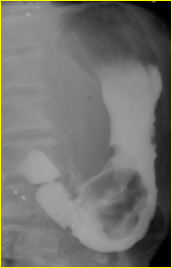

Radiologie de cancer de

estomac . Image en bourgeon . Aspect de type 2 |

|

Ulceration maligne avec

bourrelet sur eleve |